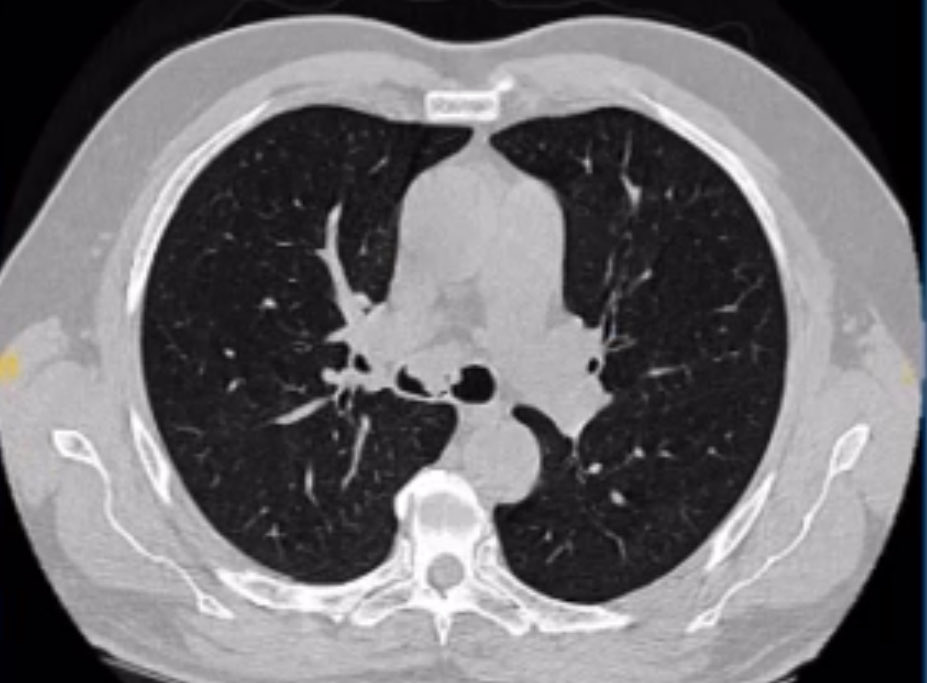

Cuando los sistemas sanitarios fallan, la Fundación Diego González Rivas tiende un puente. Eso es exactamente lo que ocurrió con una paciente peruana que cargaba durante cuatro décadas con un tumor gigante en el cuello —de 1,3 kilos de peso— sin haber encontrado en su país una solución médica viable. Fue la Fundación quien estudió su caso, asumió el compromiso de actuar y coordinó su traslado a España para recibir el tratamiento que necesitaba y operarla gracias a la colaboración del Hospital Universitario Vithas Madrid Aravaca.